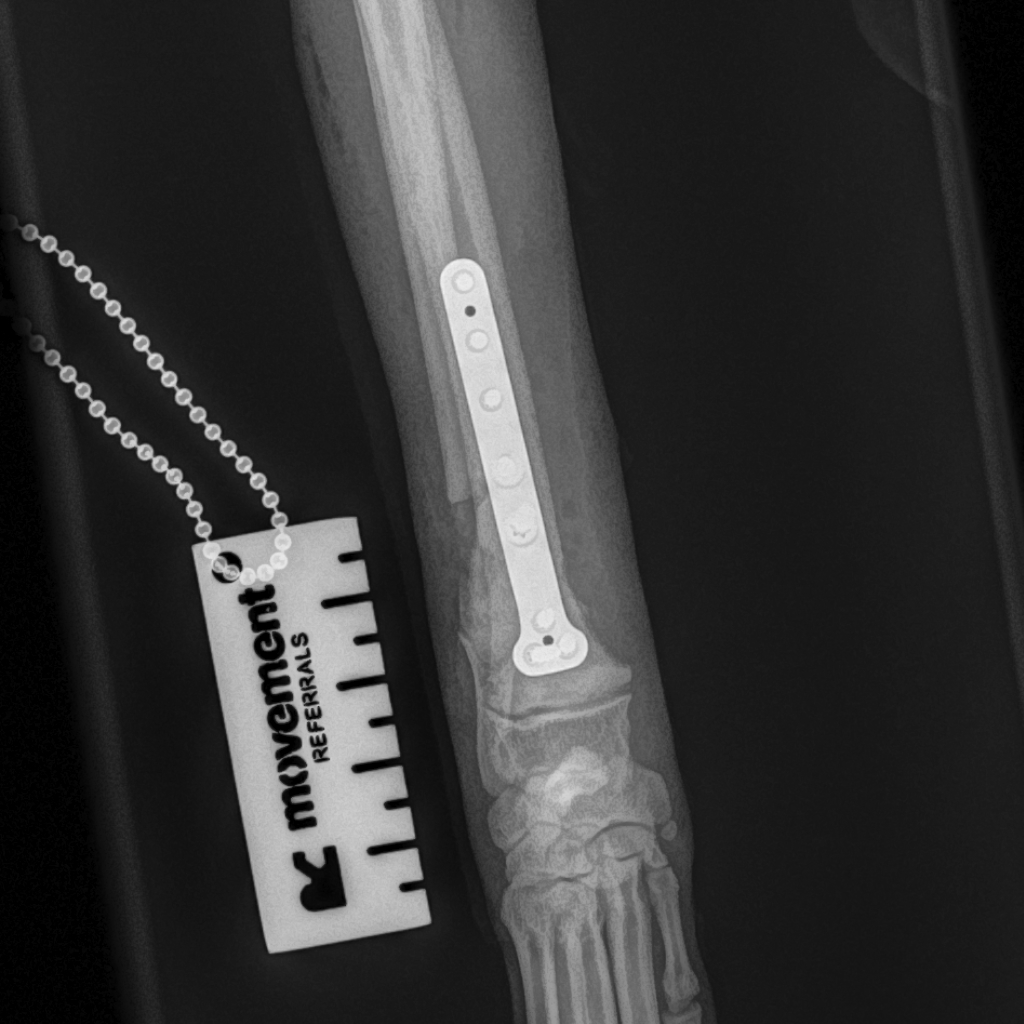

Fractures can be treated in various ways but most long-bone fractures in dogs and cats are best treated with surgery. Internal fixation is often the preferred method and may involve the use of pins and wires, or plates and screws.

At Movement Referrals, we have a range of implant systems which gives us a broad range of options to fix the full range of possible fractures in dogs and cats. Some specific examples include the Feline Lateral Ilial Plate (FLIP; Fusion Implants) and the Lateral Epicondylar Anatomical Pate (LEAP, Fusion Implants).